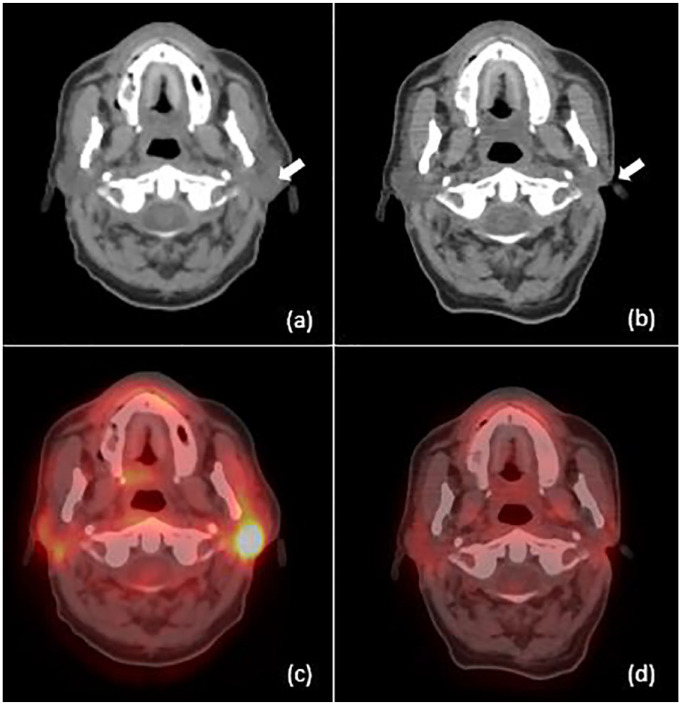

Case presentation: A 57-year-old male patient of north African origin presented with a left parotid mass that had been evolving for 6 months. He was previously diagnosed with and treated for nasopharyngeal carcinoma 2 years prior to admission, with Intensity-Modulated Radiotherapy (IMRT) without sparing the parotid gland, as well as chemotherapy. Medical imaging was suggestive of recurrence of nasopharyngeal carcinoma and metastasis due to the patient's medical history. The patient benefited from a total parotidectomy; The histopathological analysis of the surgical specimen confirmed the presence of a poorly differentiated carcinoma (UCNT) with nodal metastasis.